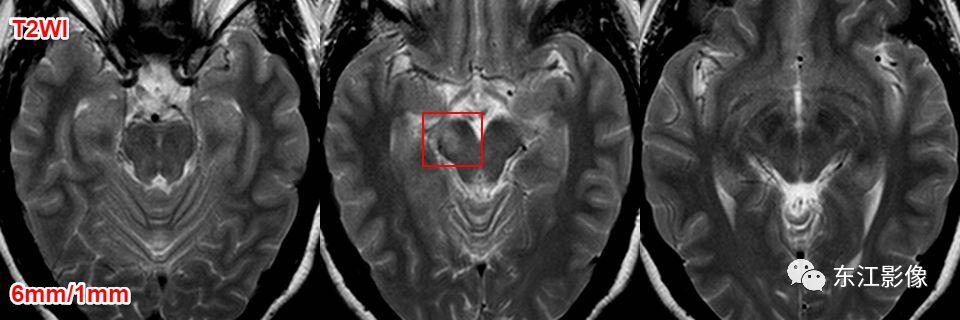

1. 扩大的血管周围间隙

扩大的血管周围间隙非常常见。

高场强、薄层扫描的话,每一个人都可见,无论老幼、男女。

部位

- 常见部位:前穿质区,外囊区,额顶叶皮层下,中脑。——务必熟记!

- 其他部位:丘脑,颞枕叶皮层下,侧脑室周围白质,小脑。

形态

- 纺锤样,泪滴状。

信号

- 与脑脊液一致。

血管周围间隙常见分布。

前穿质区VRS经典CT、MRI影像。

侧脑室顶区周围白质也是VRS的常见部位。